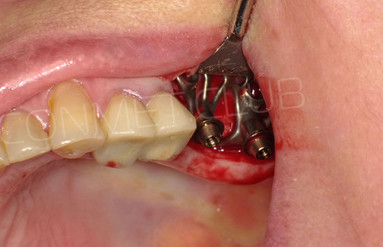

Сама же операция длиться 20-50 минут в зависимости от количества утраченных зубов. В процессе этой операции, после проведенной местной анестезии, делается разрез на слизистой, она приподнимается и субпериостальный имплантат укладывается на кость. После этого рана фиксируется несколькими швами и все! Через 10-14 дней мягкие ткани срастаются и надкостница надежно удерживает имплантат на месте. Нет необходимости ждать несколько месяцев, как это бывает в случае с внутрикостными винтовыми имплантатами.

Новые, искусственные зубы фиксируются к этому имплантату стандартными, трансокклюзионными винтами на 1-14 день (в данном клиническом случае на 5 сутки) и по существу являются несъемными!

И в-четвертых: небольшой фрагмент из операции по восстановлению всех утраченных зубов на верхней челюсти. По сути эта операция полностью повторяет протокол и этапность операции представленной в первой части статьи, за исключением того, что искусственные зубы были зафиксированы сразу после операции. Со слов самой пациентки, процесс жевания был совершенно безболезненным с самого первого дня.